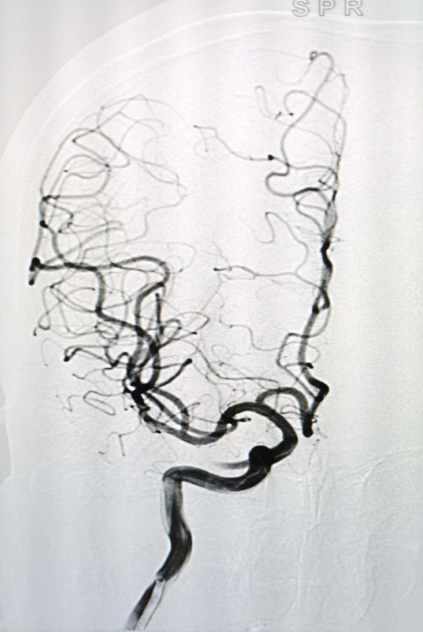

▲从左到右:术后右侧颈内动脉正位造影、术后右侧颈内动脉侧位造影

神经外科二病区在我院先行开展了脑血管造影检查,此次又率先开展神经介入治疗,不仅实现了陇南市及周边地区之前仅仅能做造影检查到现在能够完成介入治疗的重大跨越,而且填补了我市及周边地区介入治疗的空白,也标志着我市乃至甘肃南部地区神经介入发展进入新时代。